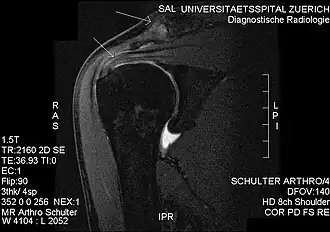

Impingement syndrome can be diagnosed by a targeted medical history and physical examination,[13][14] but it has also been argued that at least medical imaging[15] (generally X-ray initially) and/or response to local anesthetic injection[16] is necessary for workup. However, imaging studies are unable to show cause of shoulder pain in diagnosing. For example, MRI imaging would show rotator cuff pathology and bursitis but is unable to specify the cause.[17]

Plain x-rays of the shoulder can be used to detect some joint pathology and variations in the bones, including acromioclavicular arthritis, variations in the acromion, and calcification. However, x-rays do not allow visualization of soft tissue and thus hold a low diagnostic value.[2] Ultrasonography, arthrography and MRI can be used to detect rotator cuff muscle pathology. MRI is the best imaging test prior to arthroscopic surgery.[2] Due to lack of understanding of the pathoaetiology, and lack of diagnostic accuracy in the assessment process by many physicians,[21] several opinions are recommended before intervention.